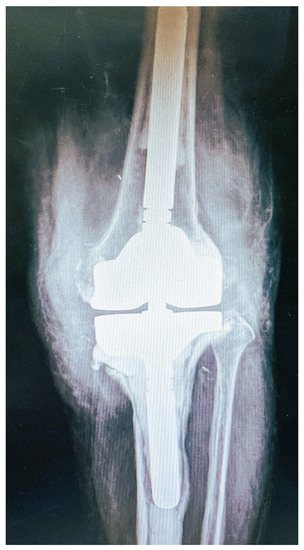

2. Case Presentation